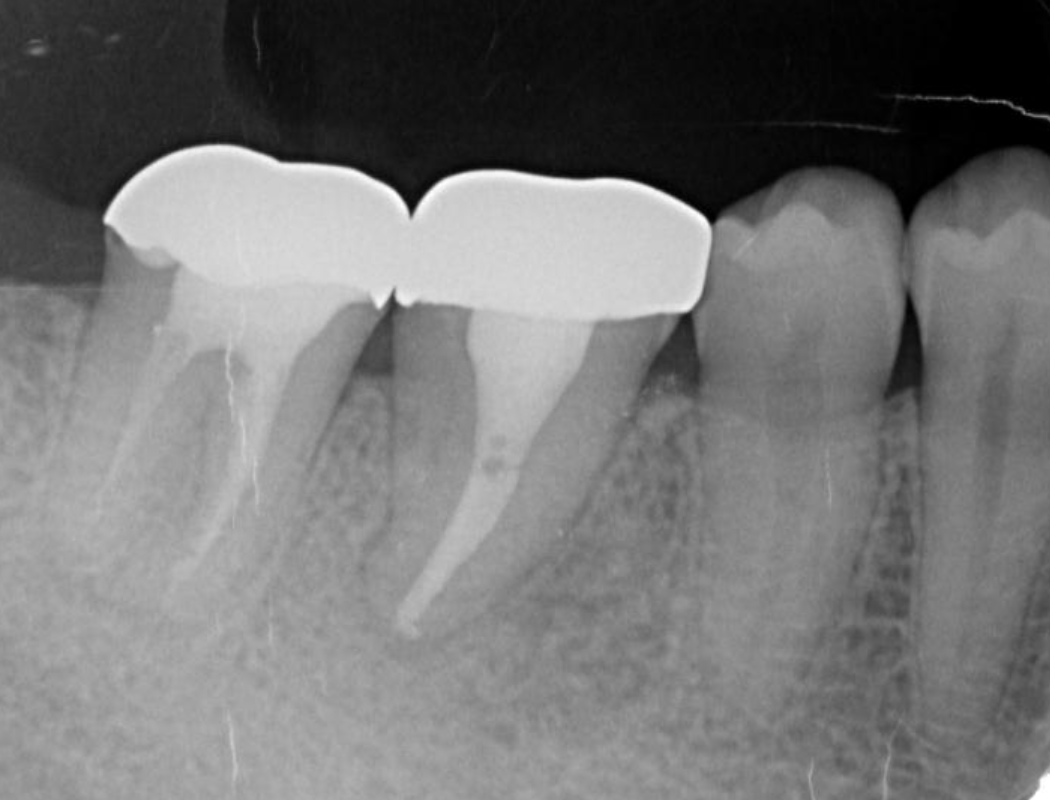

Following the operation, root canal treatment was performed as noted above. Functions including temporary crown occlusal contact and tooth mobility, as well as pocket depth were also checked. All examination results clearly indicated placement of a definitive prosthesis in the patient (Figure 13, Figure 14). At a follow-up examination one year after surgery, progress in this case was determined to be good (Figure 15).

Figure 13.Dental X-ray image obtained after confirmation of definitive prosthesis. Bone regeneration can be seen around the root of the donor tooth.

Figure 14.Intraoral photo after placement of definitive prosthesis.